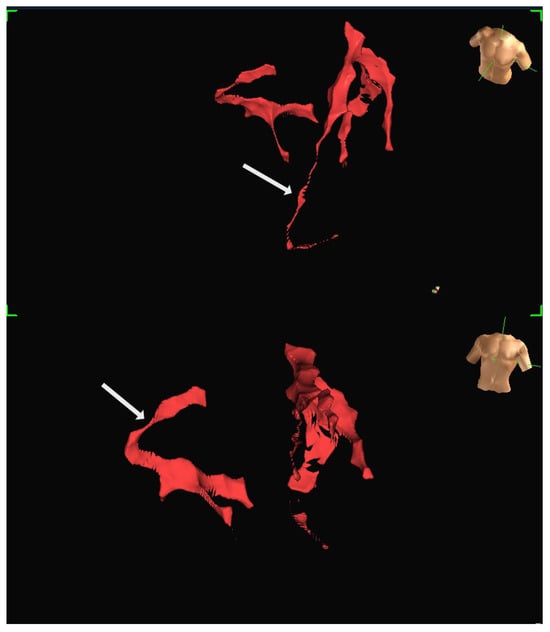

A human feasibility study involving multiple participants was conducted using the EnSite Precision system [13]. Insulated Sion Blue coronary guidewires (Asahi Intec, Japan) were tracked through epicardial arteries, including the left anterior descending and right coronary arteries, to produce anatomical reconstructions closely matching conventional angiographic images. The mapping system tracked the distal wire tip based on impedance field localisation. System accuracy was further evaluated in a custom-built water bath model incorporating segmented CT data. In this controlled setup, bipolar catheters fabricated from over-the-wire balloons and coronary wires were advanced through fixed vessel phantoms, confirming consistent localisation and map generation. Representative three-dimensional reconstructions generated using the EnSite Precision mapping system are shown in Figure 4 and Figure 5. These panels depict different views from the same patient, illustrating how coronary anatomy was mapped and visualised during the feasibility study.

Figure 4. Representative three-dimensional reconstruction of coronary anatomy generated using the EnSite Precision EAMS. The geometry was derived from guidewire tracking in a single patient. The coronary vessels are displayed in red: (Top) Left anterior oblique (LAO) projection, with the RCA marked by an arrow. (Bottom) Right anterior oblique projection (RAO), with LAD marked by an arrow. Torso icons indicate image orientation.